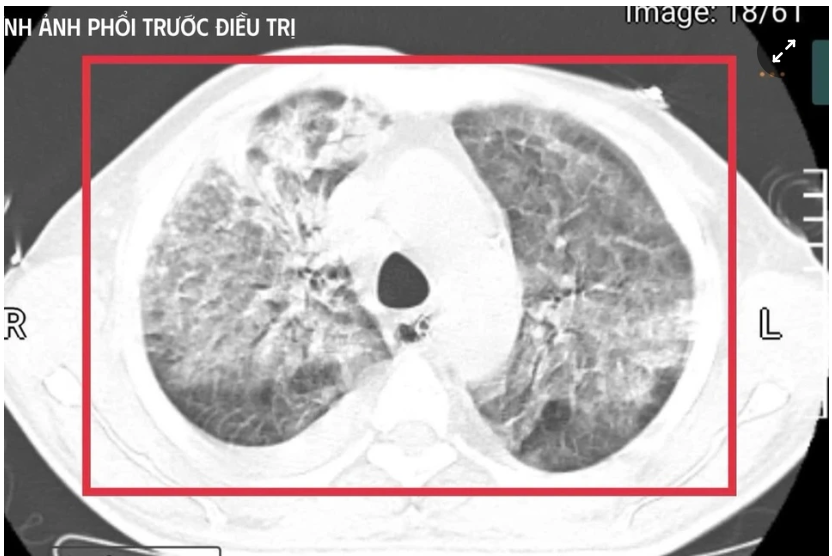

Old  Default Người đàn ông trở về từ Thái Lan, mang theo vi khuẩn 'tử thần', là gì?

Bệnh nhân 35 tuổi từ vùng lưu hành vi khuẩn mang bệnh Whitmore trở về trong tình trạng nguy kịch, sốc nhiễm khuẩn, suy đa tạng, thân nhiệt hơn 41°C và hôn mê sâu.

Bệnh nhân được xác định nhiễm Burkholderia pseudomallei - tác nhân gây bệnh Whitmore. Ảnh: BVCC.

Bệnh nhân nam L.V.T. (35 tuổi, quê Nghệ An) sinh sống và làm việc tại Thái Lan - khu vực lưu hành bệnh Whitmore cao. Anh có tiền sử đái tháo đường mới phát hiện. Khoảng 5 tuần trước khi về Việt Nam, người đàn ông xuất hiện sốt cao liên tục, khó thở, kích thích nhiều, phải nhập cấp cứu tại một cơ sở y tế ở Thái Lan.

Tại đây, bệnh nhân được đặt nội khí quản thở máy; kết quả cấy máu xác định nhiễm Burkholderia pseudomallei - tác nhân gây bệnh Whitmore. Dù được điều trị ban đầu, tình trạng vẫn diễn tiến nặng nên gia đình xin chuyển về Việt Nam để tiếp tục điều trị. Nhưng chỉ sau ít ngày, người đàn ông này rơi vào sốc nhiễm khuẩn, suy đa tạng, sốt cao liên tục, rối loạn ý thức và được chuyển gấp ra khoa Cấp cứu, Bệnh viện Bệnh Nhiệt đới Trung ương (Hà Nội).